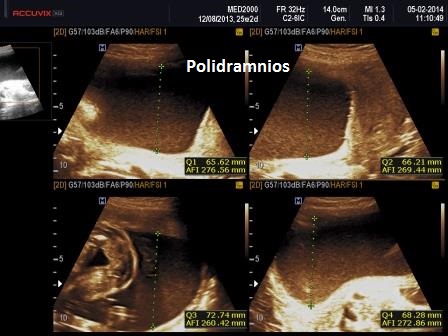

Dal punto di vista ecografico il tratto rizomelico è estremamente ipoplasico, ricurvo e con le metafisi slargate (Femore a Cornetta di Telefono) -  (il riconoscimento del Femore a Cornetta di Telefono rappresenta un segno importantissimo e sufficiente per porre con certezza la diagnosi di Displasia Tanatofora tipo I); vi sono coste corte con ipoplasia toracica e si osserva il classico gradino al passaggio tra torace ipoplasico e addome apparentemente prevalente; vi è in genere macrocrania con bozze frontali prominenti (frontal bossing) e naso a sella. Si associa polidramnios severo.

Il Polidramnios è ad insorgenza tardiva.